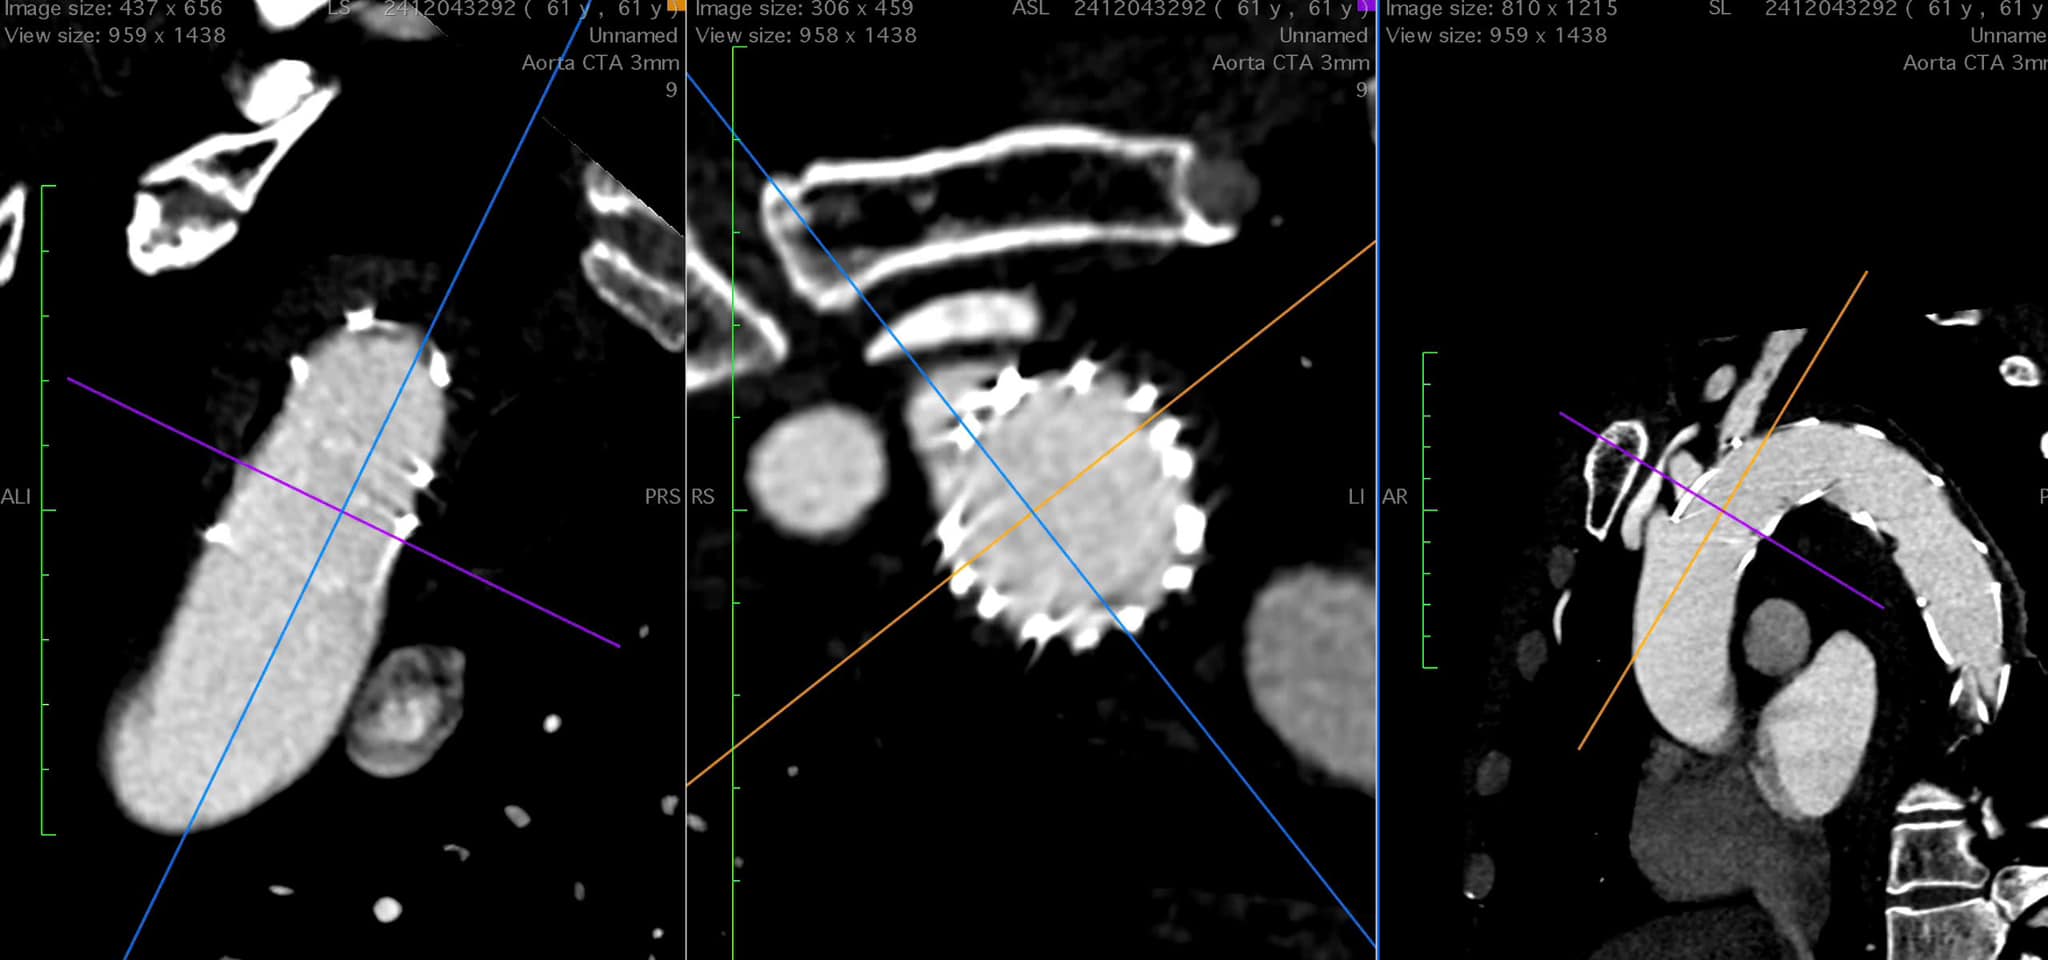

Trường hợp thứ 2 là bệnh nhân P.B.H (63 tuổi, Quảng Thắng, TP Thanh Hóa) có tiền sử suy tim giai đoạn cuối (EF 31%) do bệnh cơ tim giãn, nhập viện nhiều lần do các đợt suy tim cấp, mặc dù đã được điều trị suy tim bằng thuốc tối ưu nhưng tình trạng suy tim xấu dần qua các đợt điều trị.

Theo TS.BS. Lê Thế Anh – Trưởng khoa Nội tim mạch, Bệnh viện Đa khoa tỉnh Thanh Hóa: Phương pháp điều trị tối ưu cho trường hợp bệnh nhân H. là cấy máy tái đồng bộ cơ tim (CRT) để hỗ trợ chức năng tim. Tuy nhiên chi phí cấy máy khá tốn kém, gia đình bệnh nhân không đủ khả năng chi trả.

Trước tình trạng bệnh nặng và hoàn cảnh khó khăn của bệnh nhân, các bác sĩ khoa Nội Tim mạch đã quyết định sử dụng kỹ thuật cấy máy 2 buồng với một điện cực ở tâm nhĩ và một điện cực tại xoang vành (gọi là phương pháp LV-only) có tính năng gần như cấy máy CRT nhưng chi phí thấp hơn. Đây là kỹ thuật hiện đại và là xu hướng tạo nhịp mới trên thế giới. Tại Việt Nam, kỹ thuật này hiện mới chỉ thực hiện được ở một số Trung tâm Can thiệp của các Bệnh viện tuyến Trung ương.

Sau 20 phút thực hiện thủ thuật, bệnh nhân đã được cấy máy thành công. Ngay sau cấy máy, bệnh nhân cải thiện rõ rệt triệu chứng lâm sàng, đỡ khó thở, đi lại bình thường, các xét nghiệm sau can thiệp cải thiện tốt.